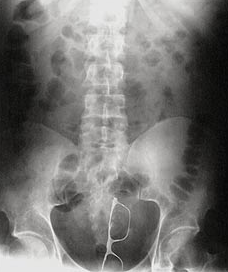

Avant de partir en vacances pour quelques semaines, je vous laisse un petit article où vous n'apprendrez pas grand chose, pour une fois, à part peut être à regarder où vous vous asseyez quand vous êtes à poil. Souvent raillé, la profession de proctologue est sûrement celle qui est le plus confronté à la mauvaise foi de ces patients. Il suffit juste de se demander comment ces derniers ont pu expliquer le résultat des radios qui suivent pour s'en convaincre.

A vous de retrouver de quoi il s'agit! Pour connaître la réponse, surlignez avec votre souris l'espace entre les crochets.